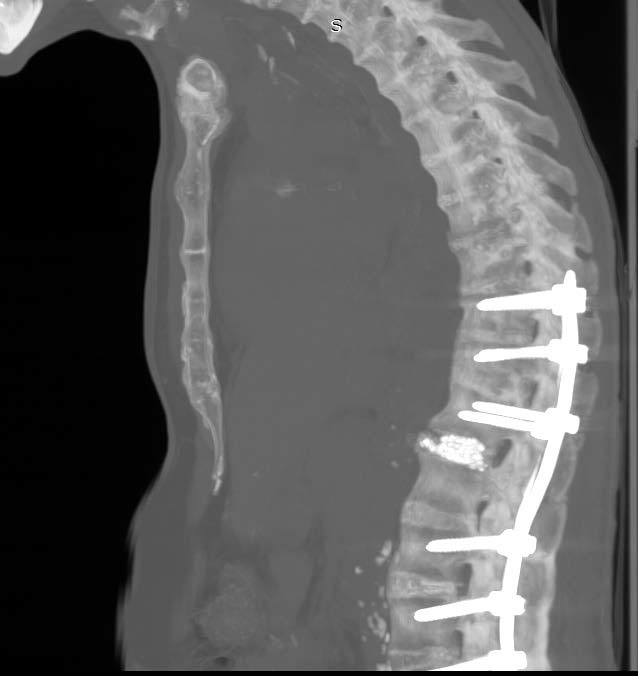

На малюнку ви можете побачити хребет по типу бамбукової палиці, який розірваний на рівні між першим та другим поперековими хребцями. Також ви можете бачити множинні осифікації у аорті, та інших внутрішніх органах.

На знімку після операції добре видно, що хребет відновив нормальну форму, а у місті розриву знаходиться кістка та штучна кістка, заповнюючи утворену порожнину та складаючи умови для вдалого зростання хребців. 12 гвинтова конструкція встановлена максимально вдало та безпечно. Надійно фіксує хребет. Таки операції супроводжуються невеликою крововтратою, за рахунок мінімальної травматичності.